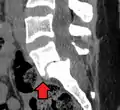

Anterolisthesis L5/S1. Blue arrow normal pars interarticularis. Red arrow is a break in pars interarticularis